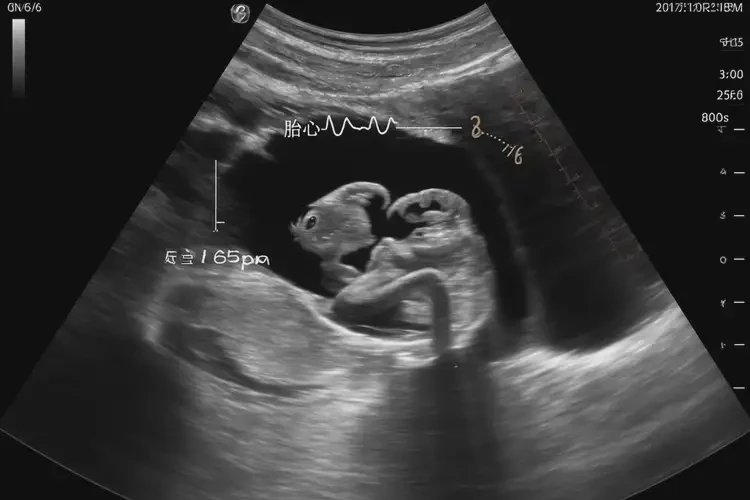

孕8周2天胎心率165怎么回事

胎心率165次/分鐘

在孕8周2天時(shí),胎心率達(dá)到165次/分鐘是正?,F(xiàn)象。胎心率是指胎兒心臟每分鐘跳動(dòng)的次數(shù),通常在孕早期(6-10周),胎心率會(huì)較快,范圍在150-190次/分鐘之間。以下是對(duì)這一現(xiàn)象的詳細(xì)解釋:

孕8周2天胎心率165怎么回事(圖1)